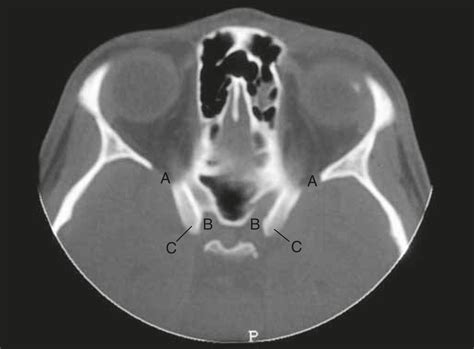

Radiological Identification

In modern neurosurgical practice, the Anterior Clinoid Process is visualized using thin-slice (0.5mm) CT scans with 3D bone reconstruction. Magnetic Resonance Imaging (MRI) is then used to map the relationship of the soft tissues—specifically the neurovascular bundle—to the bone. Recognizing the relationship between the clinoid, the optic nerve, and the ophthalmic artery on imaging is the cornerstone of safe surgical intervention.

Furthermore, the degree of ossification of the carotico-clinoid ligament—which connects the anterior and middle clinoid processes—can create a "carotico-clinoid foramen." This variation can compress the carotid artery or complicate surgical approaches, necessitating detailed preoperative imaging, such as high-resolution CT scans.